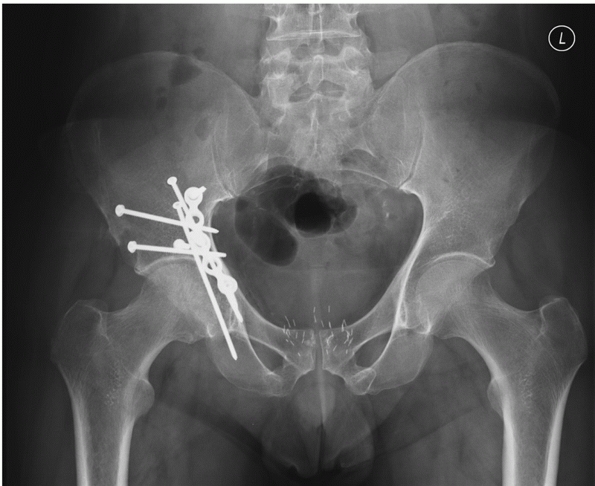

FIGURE 45-28 Radiographic appearance of the T-shaped fracture of the patient shown in Figure 45-5. A.

The appearance on the anteroposterior pelvis radiograph may be distinguished from the transverse fracture by the presence of the fracture of the ischial ramus (white arrow). Displacement of the stem of the T may cause the ilioischial line to appear duplicated (black arrowheads). Likewise, the relationship between the ilioischial line, which remains with the posterior column, and the teardrop, which remains with the anterior column, may be disrupted (black arrow). B. The obturator oblique shows the break in the iliopectineal line (black arrow). It also allows better visualization of the stem of the T (white arrow) as it enters the roof of the obturator foramen and is associated with the ischial ramus fracture (arrowhead). C. The iliac oblique view demonstrates the disruption of the greater sciatic notch and subluxation of the femoral head. (Copyright Berton R. Moed, MD.) |